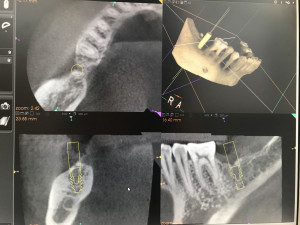

このインプラント治療をする前に特殊なレントゲン撮影(歯科用CT)で徹底的に骨の形を分析して、正しいインプラント埋入位置を計画します。

治療計画したインプラント埋入位置をデータ化してそれを3Ⅾプリンターに送るのです。このデータと、実際の口の中のデータ(現在は歯型模型)をPC上で融合させるのです。そうするとサージカルステントといってインプラント手術用の重要な道具を作ることが出来ます。いわばこれは「物差し」です。

実際のインプラント手術をする際に、このサージカルステントを口腔内にパチっとはめ込むとガイドリングがついていてインプラントの位置と埋入深度(深さ)が決まります。